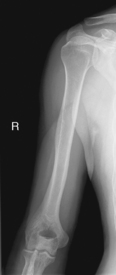

(Midhumerus and Distal Humerus)

(External and Internal Rotation)